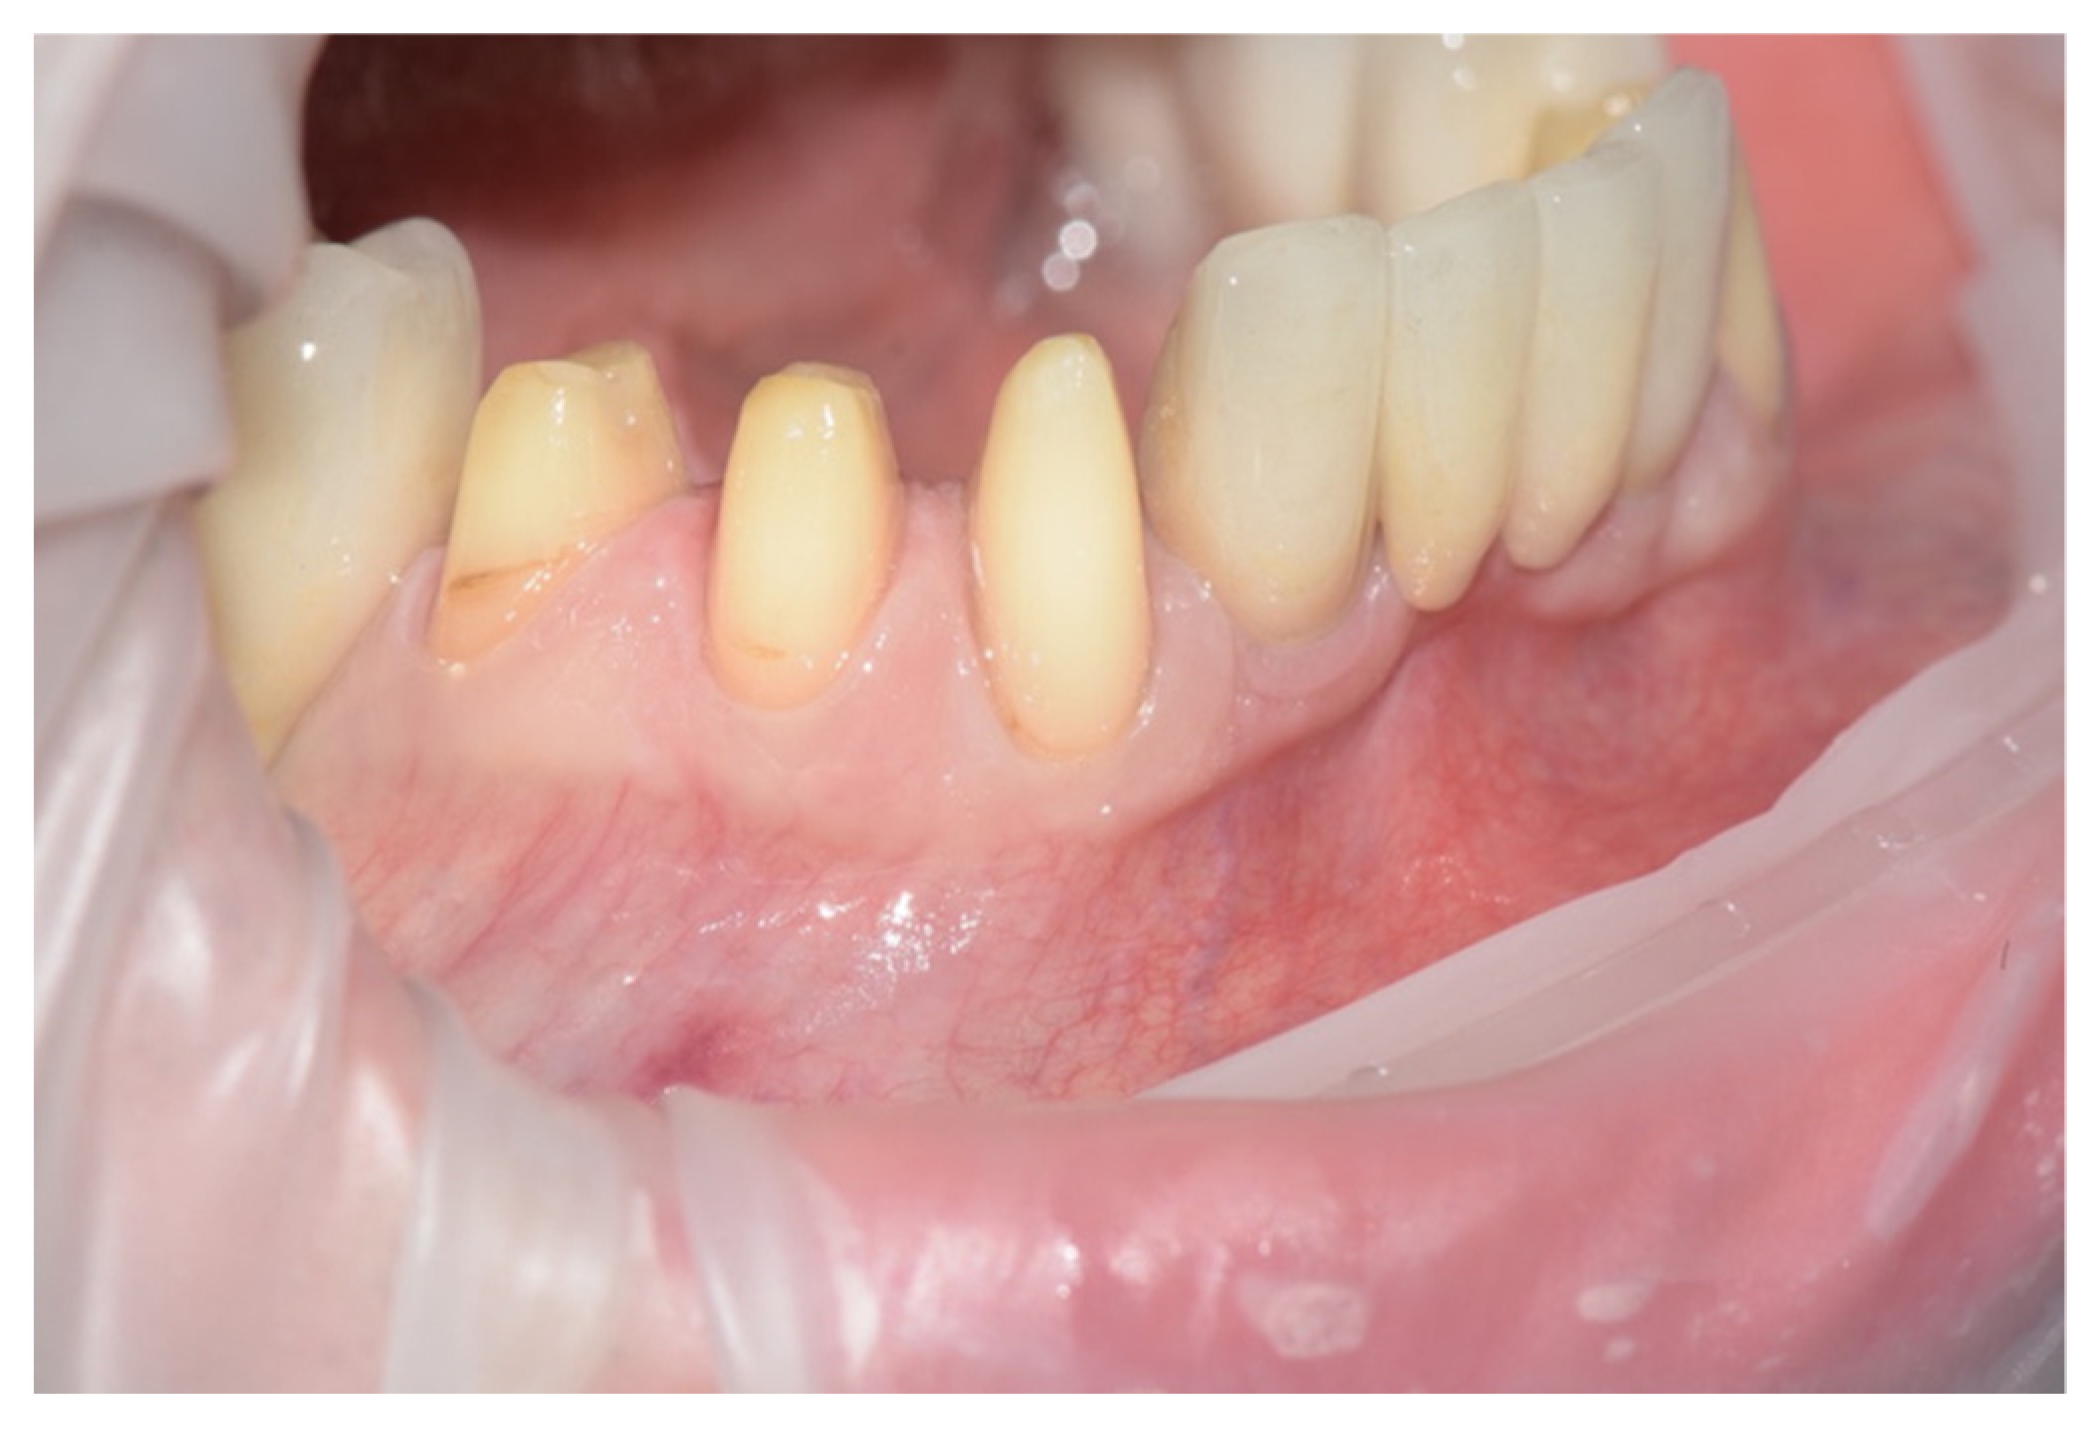

Teeth (#43, #44, and #45) were prepared with a vertical finish line at the bottom of the gingival sulcus (Figure 2) A provisional restoration made of composite material (Structur CAD, VOCO, Cuxhaven, Germany) was directly relined (Structur 3, VOCO) to achieve the optimal result in terms of function and aesthetics (Figure 3). Great care should be employed in this step, because the provisional is the source of the image of the abutments and of the sulcular morphology.

Figure 2.

Preparation of the abutments (teeth #43, #44, #45).